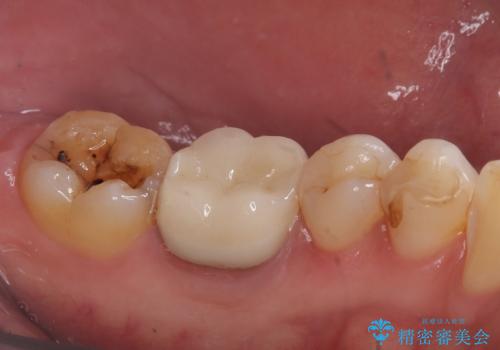

銀歯がとれた セラミックインレーで修復

- 銀歯が取れたとのことで来院されました。

拡大鏡下で丁寧に虫歯を取り除き、セラミックインレーによる修復治療を行いました。

銀歯を固着するセメントは経年劣化し溶け、隙間ができます。そこにプラークが侵入して虫歯が再発します。今回のように銀歯が脱離してしまうこともあります。

今回は銀歯が取れたので、虫歯が神経まで達して痛みが出る前に、強度・審美に優れ、虫歯の再発の少ないセラミックインレーにて治療を行うことができました。